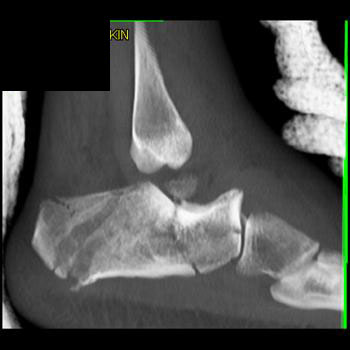

Foot Pathology: Calcaneal fractures

The calcaneus is the most commonly fractured tarsal bone. Calcaneal fractures are classified as intraarticular and extraarticular. The intraarticular fracturesaccount for 70-75% of calcaneal fractures and carry a worse prognosis. The inciting trauma is usually a fall or motor vehicle accident, and these fractures are bilateral in 10% of cases. Concomitant ipsilateral lower extremity fractures are present in 20-46% of cases, and spinal fractures in 10-30%. Extrarticular fractures (Figure: extraarticular fracture of calcaneus) account for 25-30% of calcaneal fractures, and are the sequela of a twisting injury. Anatomic regions affected include the anterior or medial process, the sustentaculum tali, the body or the tuberosity. Severe fractures are readily evident on conventional radiographs; however, CT is essential for elucidating the extent of injury. The intraarticulur fractures are often comminuted and may be displaced. CT is also used for follow up after fracture treatment. CT is very helpful for detecting fracture malunion or nonunion . In addition, the presence and extent of secondary osteoarthritis is readily detected by CT. Several features of intraarticular fractures which can be elucidated on CT have been shown to correlate with the outcome. A central depression fracture has a worse prognosis than a tongue-type fractures, but a better prognosis than a comminuted fracture. An unsatisfactory result is more likely in the setting of subtalar incongruity, decreased fibulocalcaneal space and osteoarthrosis of the talonavicular joint and the ankle.